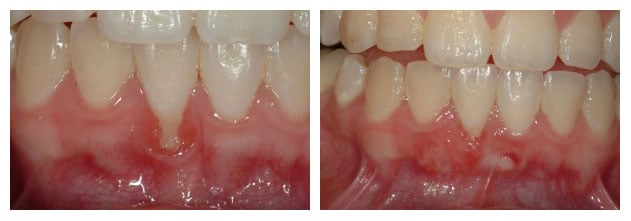

Gum Grafting, upper front teeth

Gum Grafting, upper teeth, side view

Gum Recession & Gingival Grafting